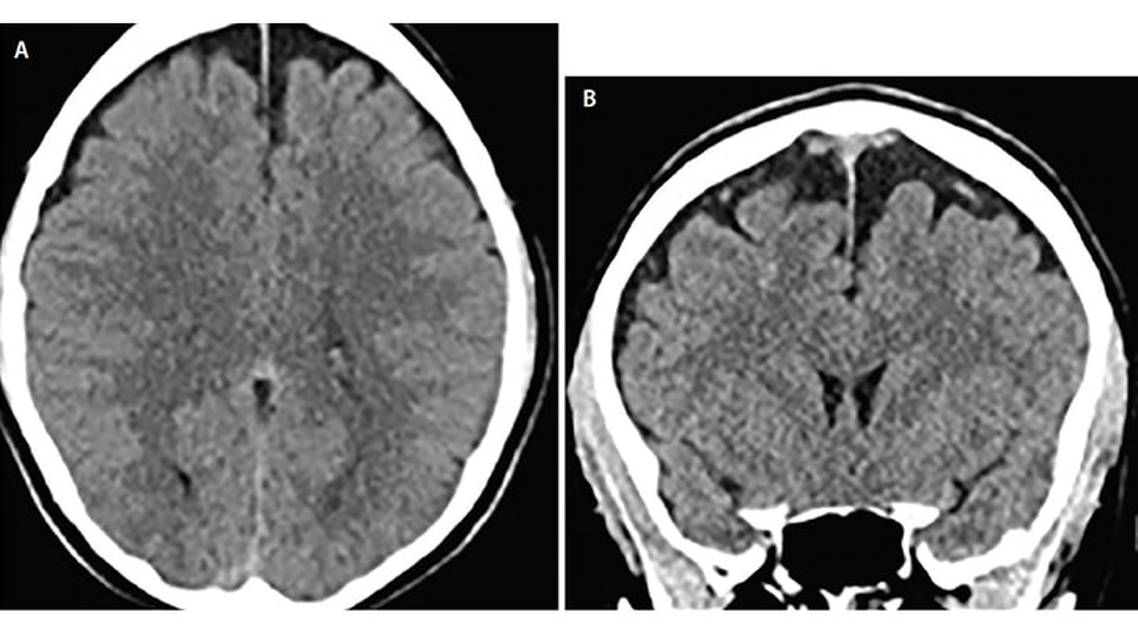

Mrs. R’s workup was negative, including findings of a noncontrast head CT (Figure 1). She had no focal neurologic deficits, and review of systems was negative except for headache, difficulty concentrating, and history of autosomal dominant polycystic kidney disease (ADPKD). She was discharged home and continued taking ibuprofen for pain relief. Mrs. R was instructed to follow up with a neurologist if her headaches persisted or worsened.

Mrs. R had bilateral subacute subdural hematomas on brain MRI 4 weeks after riding roller coasters at an amusement park. Her initial CT scan 3 days after the roller coaster trauma showed no abnormalities, but she had a persistent and worsening headache. Her presentation is consistent with a delayed subdural hematoma, which is uncommon, but has been previously reported.5